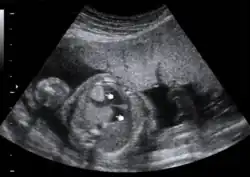

Cardiac rhabdomyomas are usually found in the ventricular walls or on the valves of the heart. With imaging techniques such as ultrasound and magnetic resonance imaging (MRI), these tumors are being detected with increased frequency and even in the prenatal period. Routine surveillance of children with tuberous sclerosis for cardiac rhabdomyoma or other cardiovascular manifestations of their disease may include electrocardiogram (EKG) and echocardiography.[12]